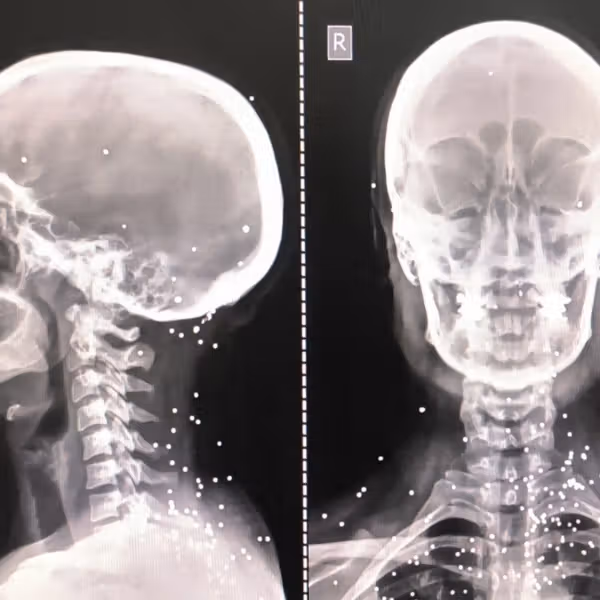

یکی از نیروهای سرکوب فعال در جنایات ۱۸ و ۱۹ دیماه، جزییات هولناکی از کشتار در تهران افشا میکند. از توزیع سلاح بین اراذل در اطلاعات سپاه پاسداران تا شلیک تیر خلاص به زخمیها، استفاده از کامیونهای یخچالدار شرکت میهن برای حمل اجساد و کندن گوشواره و گردنبند دختربچههای جانباخته.